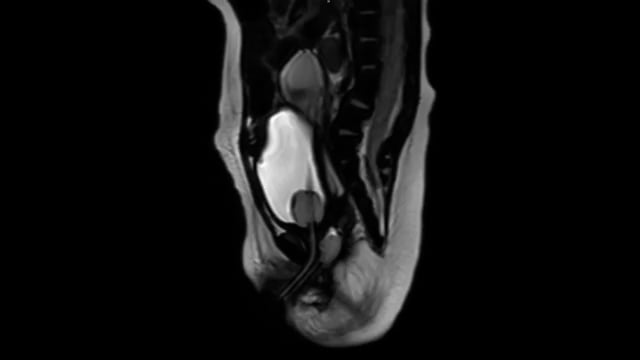

Introduction: Repair of large hiatal hernias require adequate intra-abdominal esophageal length for best long-term outcomes and less rate of recurrence. When unable to attain this length without tension, the Collis gastroplasty is an invaluable technique.

Materials and Methods: After placement of the standard 5 laparoscopic trocars for hiatal hernia repair, use of an intra-thoracically placed 45-mm stapler allows for ideal articulation though the hiatus for ligation of the fundus and creation of the neo-esophagus. Bougie placement prior is critical to protect diameter of the esophagus

Results and Conclusion: We describe the use of a laparoscopic Collis gastroplasty with Nissen fundoplication in a 14-month-old who was diagnosed with a large right-sided hiatal hernia with the gastroesophageal junction in the subcarinal position.This is an ideal technique when the gastroesophageal junction cannot be brought below the diaphragmatic hiatus without tension.